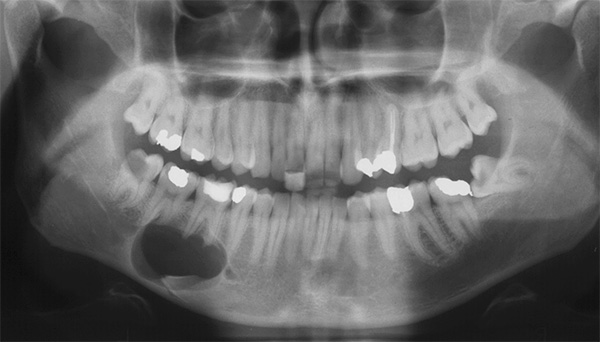

A foto abaixo mostra um exemplo de um cisto enorme, que não foi removido em tempo hábil e, tendo aumentado em volume, cresceu até as raízes de um dente adjacente:

É difícil determinar com uma imagem objetiva e mesmo com uma tomografia computadorizada com 100% de precisão que forma do processo inflamatório está presente na (s) raiz (s) do dente. Área de iluminação geralmente visível com contornos claros, geralmente arredondados ou ovais. Esse "círculo" pode ser localizado não apenas em uma raiz, mas também captura 2-3 raízes de um dente e até mesmo passa nas proximidades imediatas do topo das raízes dos dentes adjacentes, sugerindo ao dentista a escala da tragédia.

Olá O filho tem 17 anos. Recomenda-se colocar chaves. Eles tiraram uma foto panorâmica e verificou-se que havia um cisto nos seis inferiores. Diante de um dilema: um médico sugeriu que o cisto fosse removido cirurgicamente.Outro médico é categoricamente contra esse método, argumentando que há um alto risco de paresia. É realmente tão arriscado fazer uma cirurgia? Obrigada

Olá Existem muitos médicos, muitas opiniões, especialmente em situações difíceis, mas aqui não é tão simples. A proximidade do canal mandibular com a área de intervenção cirúrgica pode realmente ter certos riscos de desenvolver parestesia (de 2 a 3 semanas a vários meses, há uma sensação de dormência que não passa após uma visita ao dentista). Tais problemas nos pacientes podem ser observados mesmo após o trabalho de um especialista de primeira classe.